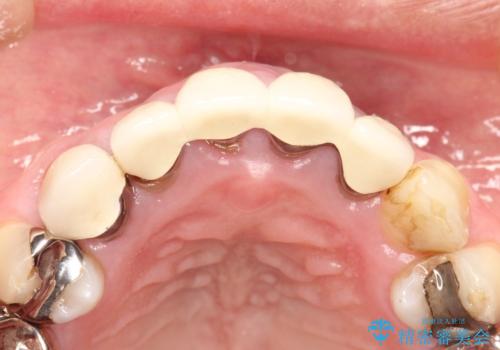

適合不良のかぶせ物をすべて除去して、根の中の治療から再治療を行うこととなりました。

適合不良のかぶせ物が装着されていた歯は、内部がやはり虫歯になっていました。

かぶせ物だけではなく見えないところも、精密な治療をすることが重要となります。